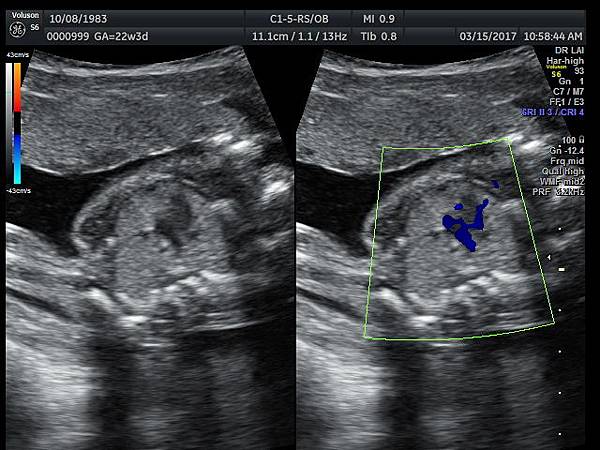

2017年3月15日33歲第一胎試管嬰兒懷孕22週3天的孕婦 、在我的診所接受胎兒心臟及高層次超音波檢查,檢查結果是單純持續性左側上腔靜脈(PLSVC),沒有合併其他異常(附圖 1~3),孕婦之前已經接受24000元的非侵入性染色體基因篩檢(NIPS),沒有異常發現,我的建議是追蹤檢查即可,如果真的很不放心,也可以考慮抽羊水做染色體及基因晶片檢查(array - CGH)。

39 22 weeks isolated PLSVC -2

38 22 weeks isolated PLSVC -1